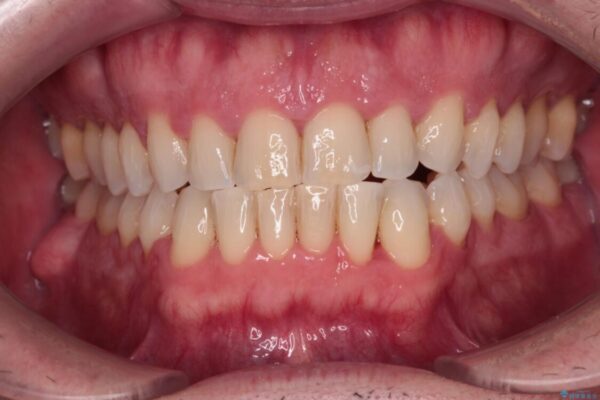

前歯でものを噛みきりたいとのことで来院された患者様です。

以前矯正治療を経験されたそうですが、舌の突出癖により上下前歯に隙間ができている様子でした。

治療前